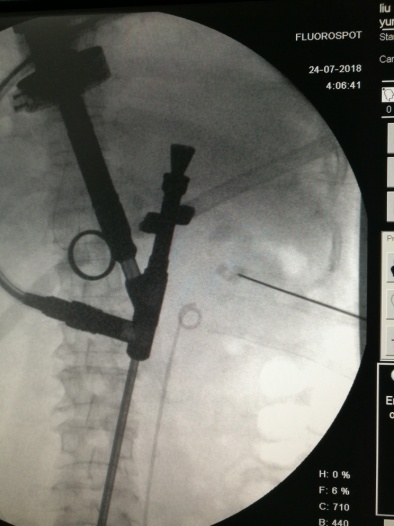

1、术前点片,确定结石位置

2、行第二个通道穿刺、结合原通道碎石

3、行第三个通道穿刺、碎石

4、极力寻找最后一部分结石

5、最后一个通道穿刺碎石,完全取尽结石

X线定位下穿刺 碎石